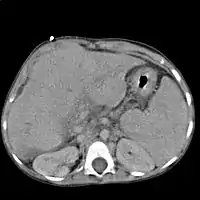

![]() Цирроз печени, приведший к гепатоцеллюлярной карциноме (макропрепарат) | |